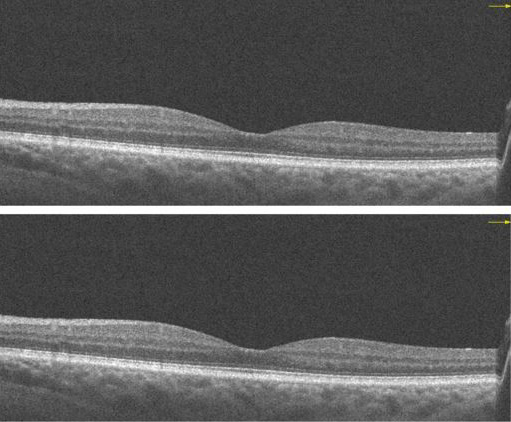

Refracting after a Vivity IOL is different than a regular refraction.